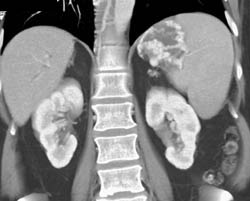

Gastric Varices